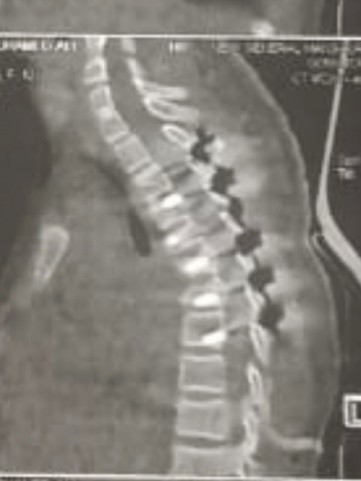

A case of kyphosis in the thoracic vertebrae of a girl at the age of ten years. The convexity was in the upper part of the thoracic vertebrae. It was caused by the impact of a solid body falling from the top of a house on the girl while she was passing under the house. This impact resulted in compression and fusion of a number of thoracic vertebrae, which led to a very, very high hunching angle, as is evident in the CT scan and MRI. Immediately after the patient was diagnosed, she was prepared for surgery to correct the deformity resulting from the kyphosis and to relieve pressure on the neural canal in the thoracic vertebrae. By the grace of God and His grace, the Almighty, the daughter was born safely to her family. The CT scan and the normal follow-up were very, very beautiful, as it was clear that the full correction of the angle of hump to the normal level.